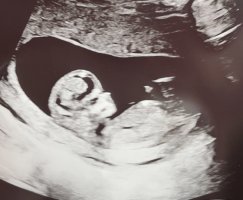

Skal jeg tippe, ville jeg sagt jenteNoen som kan se noe her?